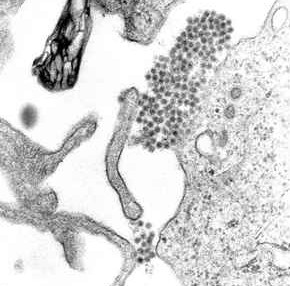

- Лихорадку Западного Нила вызывает РНК-вирус из семейства Flaviviridae. Попав в клетку и приступив к репликации, он гарантирует захваченной жилплощади долгую жизнь, а себе — множество копий, расселяющихся по организму. Передача заразы возможна только вместе с инфицированной кровью больного.

Природным резервуаром патогена являются птицы. Чтобы вирус кочевал от одного хозяина к другому, ему нужен транспорт — таковым являются клещи и комары. Маленькие кровососы недолго выбирают источник питания: если после больной птички подвернется лошадка или человек, комар получит свою порцию крови, а его жертва — инфекцию. В данный момент список живых существ, на здоровье которых может покуситься инфекция, очень широк. Помимо птиц и млекопитающих, там есть и рептилии.